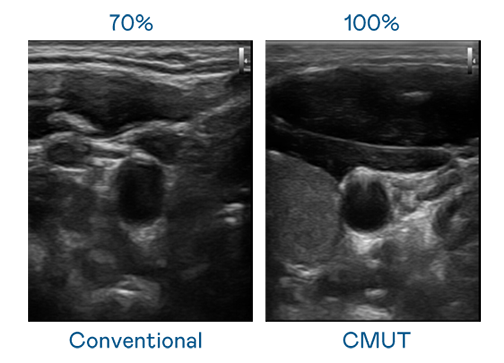

CMUT 技术是一种用电容式微机电元件来产生超音波讯号的技术。与传统 PZT 压电式技术相比,CMUT 频宽增加 30%,更宽频的超音波讯号让影像解析度大幅提升,是实现高影像品质医疗超音波扫描、促进精准医疗发展的关键技术。

大频宽带来超清晰影像

超音波影像的解析度高低,首先取决于探头能发出的讯号频宽。金沙城 CMUT 可提供高清晰的超音波讯号,提供高频宽、高灵敏度、影像纹理细节更高的超音波影像,协助医护人员缩短影像判读时间及利用精准的医疗影像进行诊断。